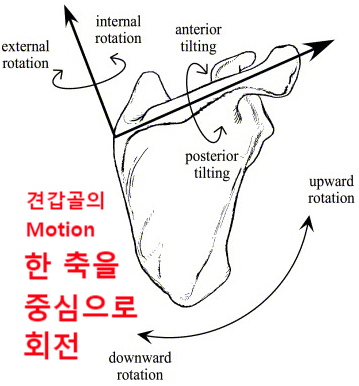

견갑골의 움직임은 3가지 움직임(Motion)과 2가지 미끄러짐(translations)으로 나눌 수 있습니다.

움직임(motion) - 한 축을 중심으로

ㆍ회전외회전(ER) / 내회전(IR)

ㆍ앞쪽 기울어짐(Anterior tilting) / 뒤쪽 기울어짐(Posterior tilting)

ㆍ상방회전(Upward rotation) / 하방회전(Downward rotation)